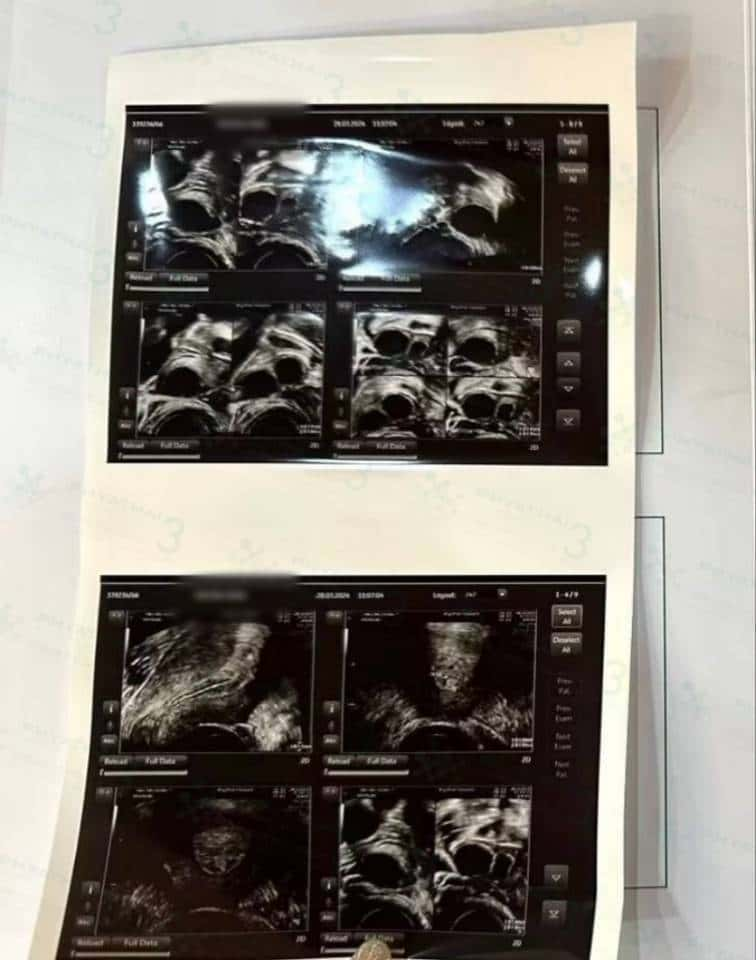

今天有机会跟我们医疗翻译一起去见诊,今天我们女士是第三次见诊了,女士今天做阴超检查了之后,库医生说;根据今天阴超结果女士的子宫内膜开始增厚了,内膜厚度是9毫米,库医生安排今晚打夜针,库医生预估了,女士可以取到卵子的机会是9-14枚左右,所以库医生给女士安排了3个品牌的夜针,明天早上六点就安排女士来医院取卵了,希望我们女士取卵顺利的哈